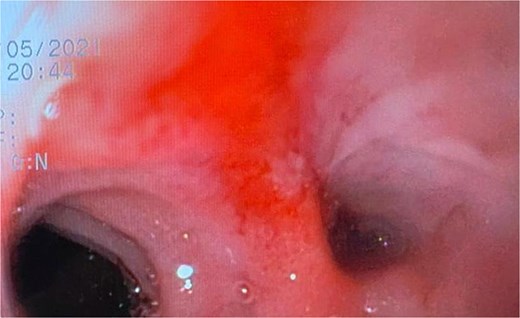

A 44-year-old female with no significant medical history underwent Roux-en-Y gastric bypass for grade III obesity (BMI 41). She presented with necrosis of the gastric pouch within the first 48 hours, leading to leakage of the gastrojejunal and jejunojejunal anastomoses. Esophagojejunal anastomosis and revision of the jejunojejunal anastomosis were performed, but the patient developed septic shock due to esophagojejunal anastomosis leakage, requiring 7 days in intensive care. Upon stabilization, she was referred to our service for endoscopic management of an esophagojejunal fistula. A 10 mm fistulous orifice was observed (Fig. 1), and EVAC therapy was initiated using a polyurethane sponge with an 8 Fr catheter at 125 mmHg continuous suction (Fig. 2). Six changes were made at 3–5-day intervals.

The placement of the catheter and sponge for EVAC therapy is observed.